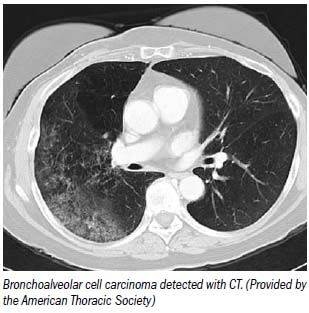

CT colonography can pinpoint cancerous colorectal segments more accurately than colonoscopy, according to Italian investigators. They say virtual, not optical, colonoscopy should be the gold standard for the preoperative staging of colorectal cancer.